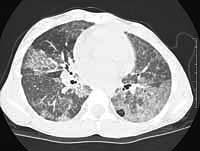

She was treated for viral pneumonia at that time and was noted to have progressively increased oxygen requirements. A high resolution computed axial tomography was done in June 2000, which showed patchy ground glass opacification, prominent azygous lobe "crazy paving" was noted. The exercise test showed that she had difficulty with the test and she had moderate hypoxemia with exercise, desaturation to 80%. Room air oxygen saturation was 89% at rest.

TABLE OF PROCEDURES AND COMPLICATIONS

Despite some improvement with the bronchial washings, she has continued to require oxygen (at 3L/min continuous) and has failure to thrive. Her weight is 22.6 kg (< 5%ile) and height (128 cm ~5%ile). Her echocardiogram is normal and she is not polycythemic as a result of hypoxemia. The pulmonary function tests show a moderate restrictive defect. Her most recent high resolution CT scan shows persistent ground glass infiltrates and crazy paving despite bronchial lavages.

CT

scans: original after first wash compared to most recent HRCT.

LEFT

CT SCAN (June), RIGHT

CT SCAN (August)